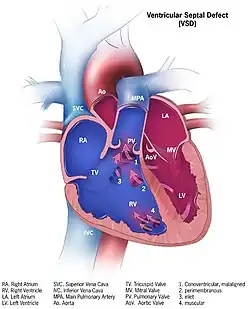

| Illustration showing various forms of ventricular septal defects. 1. Conoventricular, malaligned 2. Perimembranous 3. Inlet 4. Muscular | |

Although there are several classifications for VSD, the most accepted and unified classification is that of Congenital Heart Surgery Nomenclature and Database Project.[14] The classification is based on the location of the VSD on the right ventricular surface of the inter ventricular septum and is as follows:

Multiple

Type 1

Type 1 is sub aortic

Type 2

- Type 2 also known as perimembranous, paramembranous, conoventricular, membranous septal defect, and subaortic.

- Most common variety found in 70%

Type 3

Type 3 also known as inlet (or AV canal type).

- Commonly associated with atrioventricular septal defect, found in about 5%

Type 4

Type 4 also known as muscular (trabecular)

- Located in the muscular septum, found in 20%. Can be sub classified again based on the location into anterior, apical, posterior and mid

Type: Gerbode

Type: Gerbode also known as left ventricular to right atrial communication

- Due to absence of Atrioventricular septum.